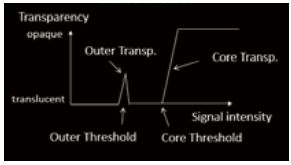

Shadow Glass - це новітня технологія візуалізації, яку можна застосувати до зображень, отриманих за допомогою Smart Sensor 3D. Цей інноваційний метод відображення дозволяє спостерігати внутрішні структури, оскільки він використовує два різні фільтри для створення напівпрозорого об'ємного зображення. У порівнянні зі звичайними 3D-зображеннями, Shadow Glass дозволяє легше спостерігати за цілісними структурами. У випадку плоду Shadow Glass дозволяє чітко роздивитись органи відносно загальної анатомії.

Рисунок 2. Схема роботи Shadow Glass

a) Візуалізація об'єму

б) Яскравість

в) Shadow Glass